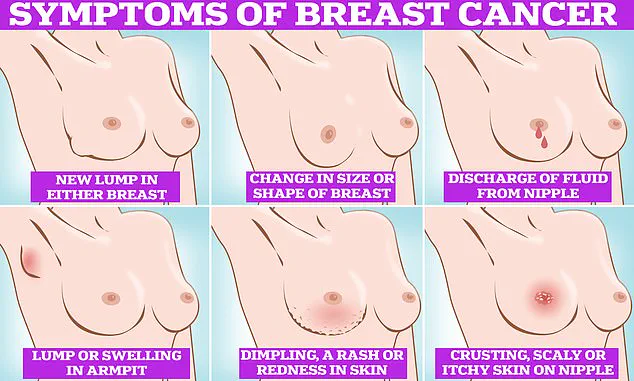

Symptoms of breast cancer to look out for include lumps and swellings, dimpling of the skin, changes in colour, discharge, and a rash or crusting around the nipple.

These signs, while not always indicative of cancer, warrant immediate medical attention.

These include a lump or swelling in the breast, chest, or armpit, a change in the skin of the breast or general change in its size and shape.

Nipple discharge with blood, a change in the shape or look of the nipple, and continuous pain in the breast or armpit are also signs of the disease.

While these are not always signs of cancer, anyone with these symptoms is advised to book an appointment with their GP so they can be checked.